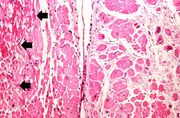

| 04:22, 19 August 2013 | IPLab3BrainInfarction4.jpg (file) | 68 KB | Seung Park | This is a photomicrograph of the edge of the infarct. Note the numerous inflammatory cells in the brain parenchyma and adjacent to the remaining brain tissue (arrows). | 1 | |